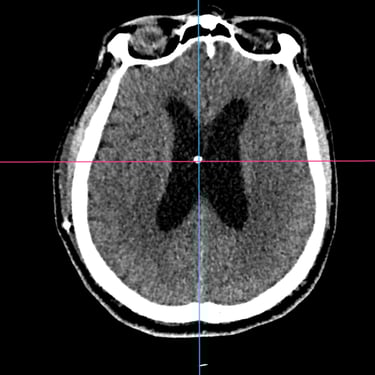

La hidrocefalia es una condición caracterizada por la acumulación anormal de líquido cefalorraquídeo en los ventrículos cerebrales, lo que genera aumento de la presión intracraneal y síntomas como cefalea, náuseas, alteraciones cognitivas y trastornos de la marcha. Cuando el manejo médico no es suficiente, la derivación ventriculoperitoneal (DVP) es el tratamiento quirúrgico más utilizado. Este procedimiento permite drenar el exceso de líquido desde el cerebro hacia la cavidad abdominal, donde es reabsorbido, aliviando la presión intracraneal y mejorando la función neurológica. El tratamiento oportuno es clave para prevenir secuelas.